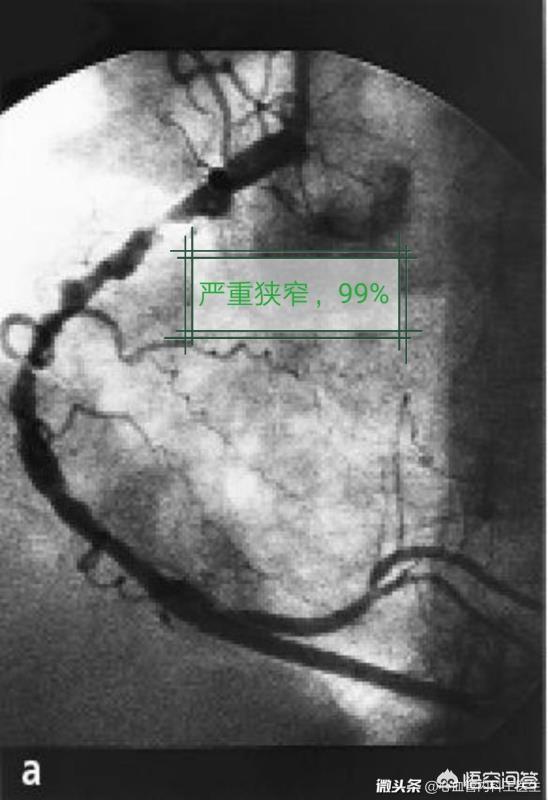

Patienten mit einer leichten Verengung der Herzkranzgefäße, einer Verengung mit geringer Auswirkung auf den Blutfluss oder einigen kleineren Gefäßverzweigungen von geringerer Bedeutung werden in der Regel nur mit Medikamenten behandelt und dann regelmäßig zur Beobachtung nachuntersucht. Wenn zu diesem Zeitpunkt ein Stent implantiert wird, kann er mehr schaden als nützen.

Vermeidung von Risikofaktoren: Bei der koronaren Herzkrankheit handelt es sich um eine atherosklerotische Erkrankung, die eine Systemerkrankung ist, und beim Stenting werden nur Läsionen mit einer Koronarstenose von mehr als 70 % behandelt, und sicherlich gibt es noch viele andere sklerotische Läsionen, so dass die Vermeidung von atherosklerotischen Risikofaktoren nach dem Stenting besonders wichtig ist. Es gibt einen solchen Patienten, nachdem ein Stent in das Herz eingesetzt wurde, verbesserten sich die Brustschmerzsymptome deutlich, aber nachdem er nach Hause ging, rauchte er immer noch, blieb lange auf, bewegte sich nicht und hatte einen anderen schlechten Lebensstil, dann traten die Symptome in den nächsten 3 Jahren wieder auf, und dann wurden kontinuierlich 2 Stents eingesetzt, so dass der Stent nur die symptomatische Behandlung ist, und die Vermeidung von Risikofaktoren ist die eigentliche Ursache der Krankheit!

2.Verbesserung der gesamten Koronarläsionen durch Stentimplantation. Wir sagen, dass das Stenting eine Methode der Koronarrevaskularisierung ist. Wenn der Patient eine einzelne Läsion in einem einzigen Gefäß hat, führt das Stenting zu einer vollständigen Umgestaltung des Blutflusses und zu einer Verbesserung der gesamten Blutversorgung des Herzmuskels, was natürlich langfristig die Lebensqualität verbessert. Wenn der Patient jedoch mehrere Gefäße mit mehreren Läsionen hat, löst die Implantation eines Koronarstents nur das lokale Problem, und die Verbesserung der Gesamtdurchblutung des Herzmuskels ist begrenzt, so dass auch die Verbesserung der Lebensqualität begrenzt sein wird.